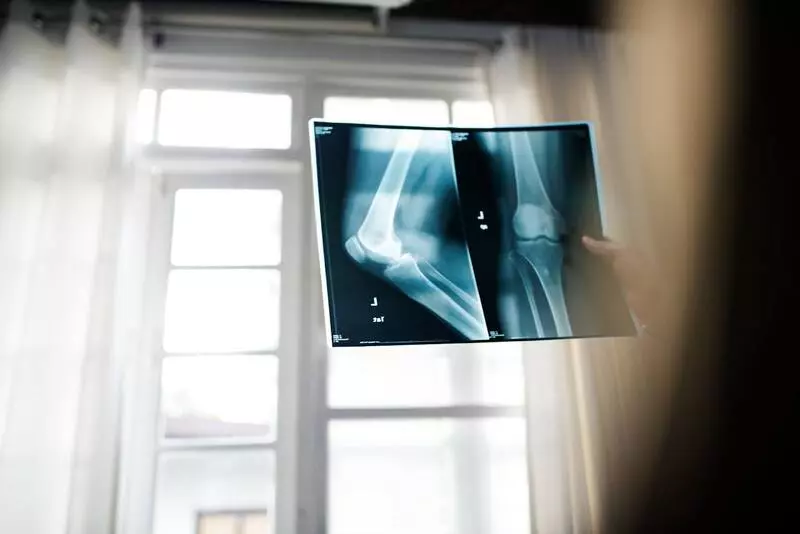

3. Рентгенография. Показывает степень сужения суставной щели, изменения костных поверхностей.

4. МРТ и КТ. Используются для точной оценки состояния хряща, связок и мягких тканей.